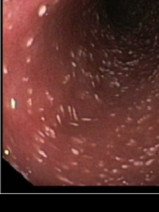

• Formation pratique en endoscopie digestive et respiratoire - Niveaux 1 & 2

L’AFVAC organise une formation pratique d’endoscopie digestive et respiratoire.

Cette formation pratique se déroule pendant trois journées sur le plateau technique exceptionnel de l’École de Chirurgie de Nancy. Grâce à la présence de moniteurs qualifiés, elle s’adresse aussi bien au praticien souhaitant améliorer sa technique qu’au débutant en endoscopie. La simulation sous toutes ses f...